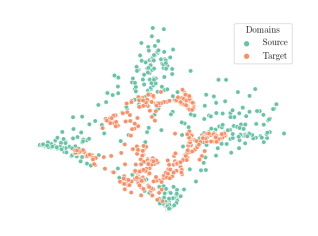

We compare the -distance of categorical features and domain features. Fig. 5 (a) shows that domain difference is higher in domain features than in categorical features. This indicates that domain features contain more domain information whereas categorical features are more domain-invariant. Fig. 6 shows the t-SNE plot of categorical features in both domains for MIDNet. From Fig. 6 (a), we observe that the categorical features learned by MIDNet enable the anatomical classification. Fig. 6 (b) shows that the learned categorical features are domain-invariant.

In addition, we utilize t-SNE plots for feature visualization in Fig. 10. Comparing Fig. 10 (a) and Fig. 10 (b), we observe that with mutual information disentanglement, (1) samples from the same category are more tightly clustered (see the top row) and (2) the source domain and the target domain are overlap more (see the bottom row). This indicates that mutual information disentanglement is important for learning categorical-focused and domain-invariant features. Fig. 10 (a), (c)-(d) show that the proposed method outperforms other state-of-the-art methods for learning category-discriminative and domain-invariant features, especially for unseen categories in the target domain (e.g., (a) vs. (d)).